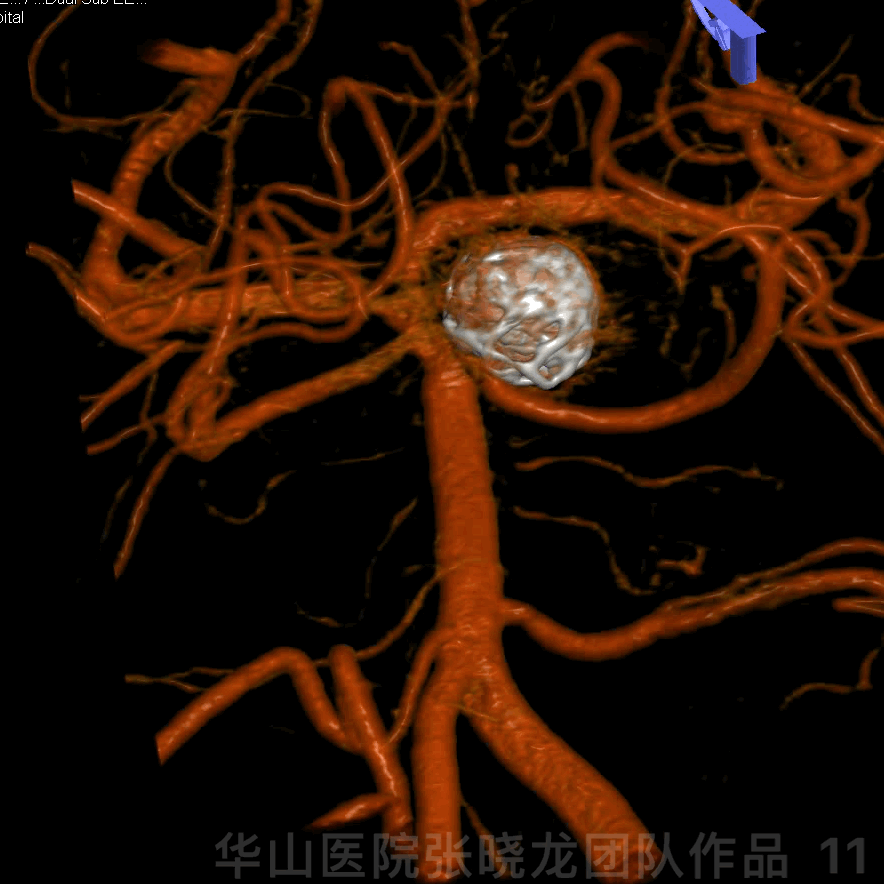

Figure 11 GIF. 3D construction.

图 11 GIF. 3D重建。